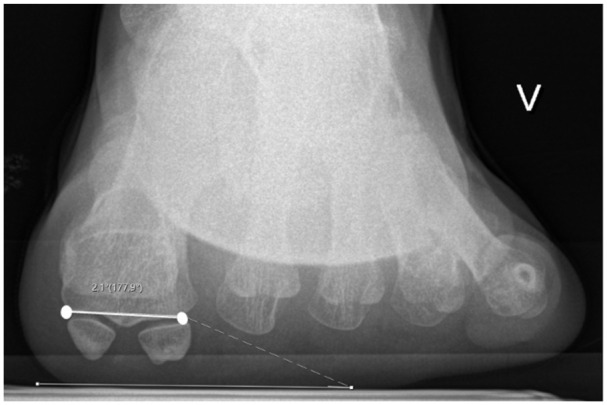

背景:第一跖骨旋转错位越来越被认为是拇外翻畸形的一个关键特征,但x线旋转标记物的可靠性仍然不确定。本研究评估了4个常用的影像学参数:跖骨旋前角(MPA)、胫骨sesamoid位置(TSP)、侧头形状(LHS)和圆头征象(RH)在观察者间和观察者内的可靠性。方法:在这项前瞻性可靠性研究中,3名资深临床医生独立评估了75例2次拇外翻的负重正位和轴位籽骨片。测量跖骨旋前角(MPA)作为连续变量,并使用类内相关系数(ICCs)进行分析。采用顺序量表对胫骨籽骨位置(TSP)、侧头形状(LHS)和圆头标志(RH)进行评分,并采用加权kappa统计量(κ)进行评估。亚组分析评估了可靠性是否因畸形严重程度(拇外翻角)或远端跖关节角(DMAA bbb10度)的增加而变化。结果:MPA具有良好的一致性(ICC = 0.81 ~ 0.94)。TSP也表现出高可靠性(κ = 0.88-0.98),尽管其作为旋转标记的价值有限。LHS具有中等至基本的一致性(κ = 0.59-0.85),而RH具有中等至中等的可靠性(κ = 0.35-0.66)。RH在轻度畸形中最不可靠,而其他参数在亚组中保持稳定,在DMAA升高的情况下值略低。结论:常规x线片可可靠评估MPA和TSP。LHS提供了可接受的再现性,而RH则不太一致。这些发现支持选择放射学标记物的使用,并表明针对三维成像和标准化分级框架的进一步验证可能会提高一致性和临床适用性。证据等级:四级,案例系列。

Methods: In this prospective reliability study, 3 senior clinicians independently evaluated weightbearing anteroposterior and axial sesamoid radiographs of 75 hallux valgus cases on 2 occasions. Metatarsal pronation angle (MPA) was measured as a continuous variable and analyzed using intraclass correlation coefficients (ICCs). Tibial sesamoid position (TSP), lateral head shape (LHS), and round head sign (RH) were graded using ordinal scales and assessed with weighted kappa statistics (κ). Subgroup analyses evaluated whether reliability varied by deformity severity (hallux valgus angle) or increased distal metatarsal articular angle (DMAA > 10 degrees).